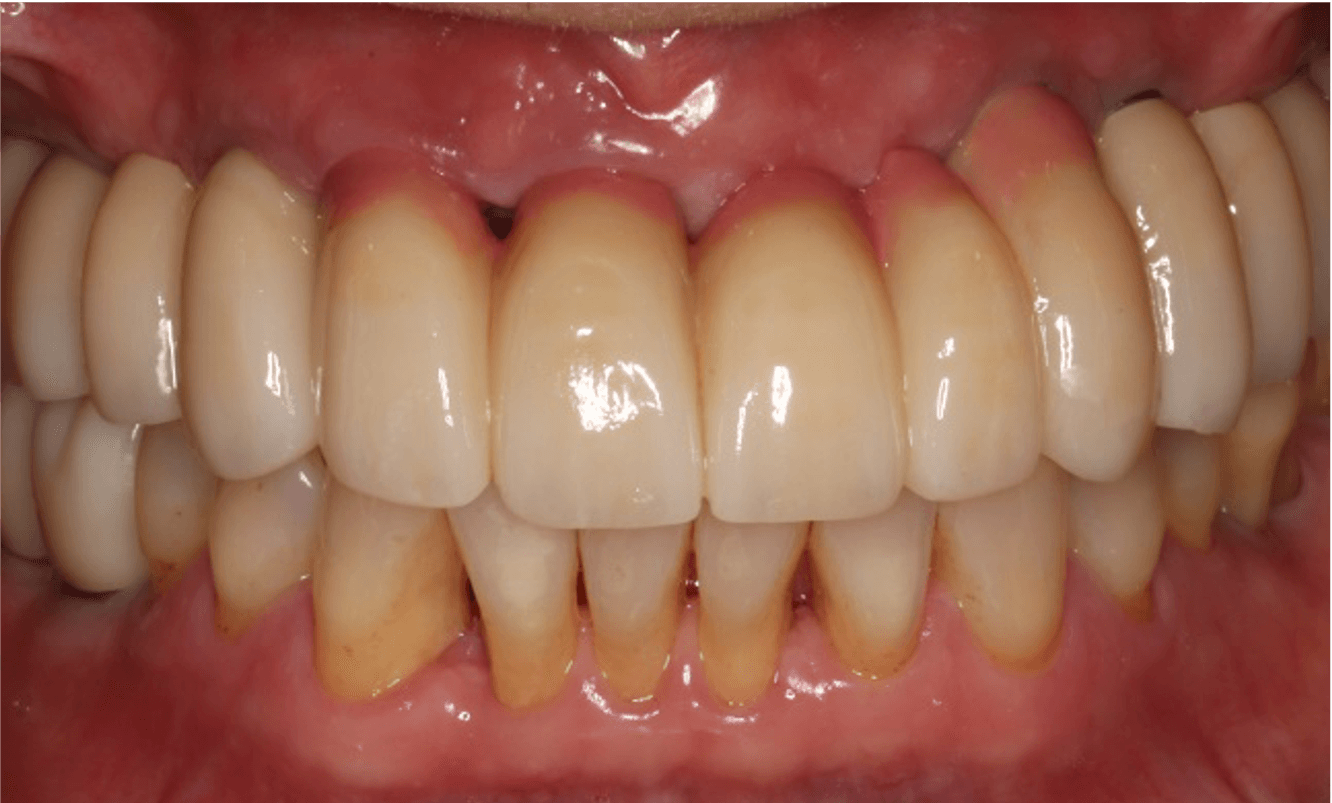

치료 전후 비교

치료 전

치료 후

본 이미지는 촬영 조건에 따라 실물과 일부 다르게 보일 수 있으며, 환자 본인의 동의를 얻어 촬영 후 게재하였습니다.

치료 결과는 환자 개개인의 상태에 따라 다르며, 치과의사의 상담이 필요합니다.